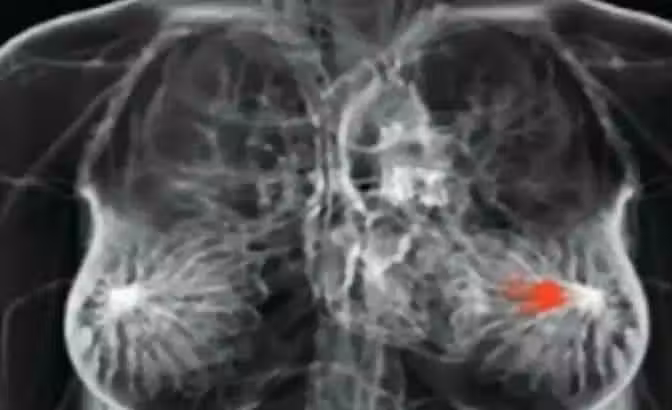

身體發生「4狀況」是「乳癌」前兆!別再只靠手摸「胸部腫塊」測腫瘤 女性朋友一定要知道!

所以我們總是特別注意癌症前身體會發生的徵兆,根據《TTAC》的報導,我們要來告訴大家不常被大家提起的乳癌徵兆。

如果你還認為在乳房中發現了一個局部疼痛的獨立腫塊,就是乳房發生癌症的跡象的話,那你可能就錯了!事實上,乳癌出現的腫塊其實都是分散在乳房的各處,像是種子一般的,甚至在某些情況很多乳癌患者是根本沒有腫塊的。